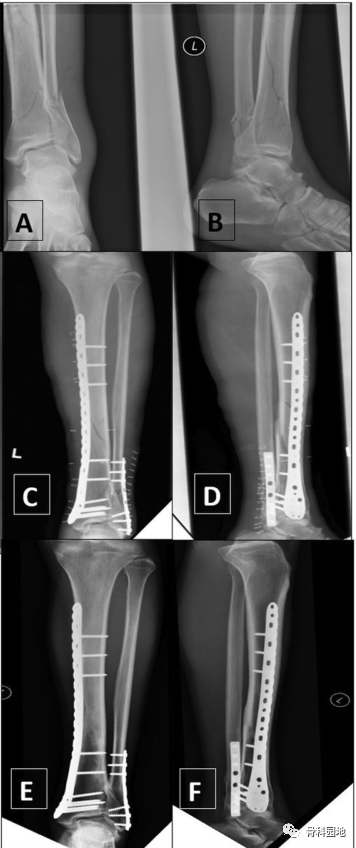

一、没有腓骨固定的情况下使用前外侧胫骨远端钢板固定骨折

二、使用内侧胫骨板和腓骨钢板固定。

三、使用前外侧钢板固定胫骨和腓骨克氏针固定。